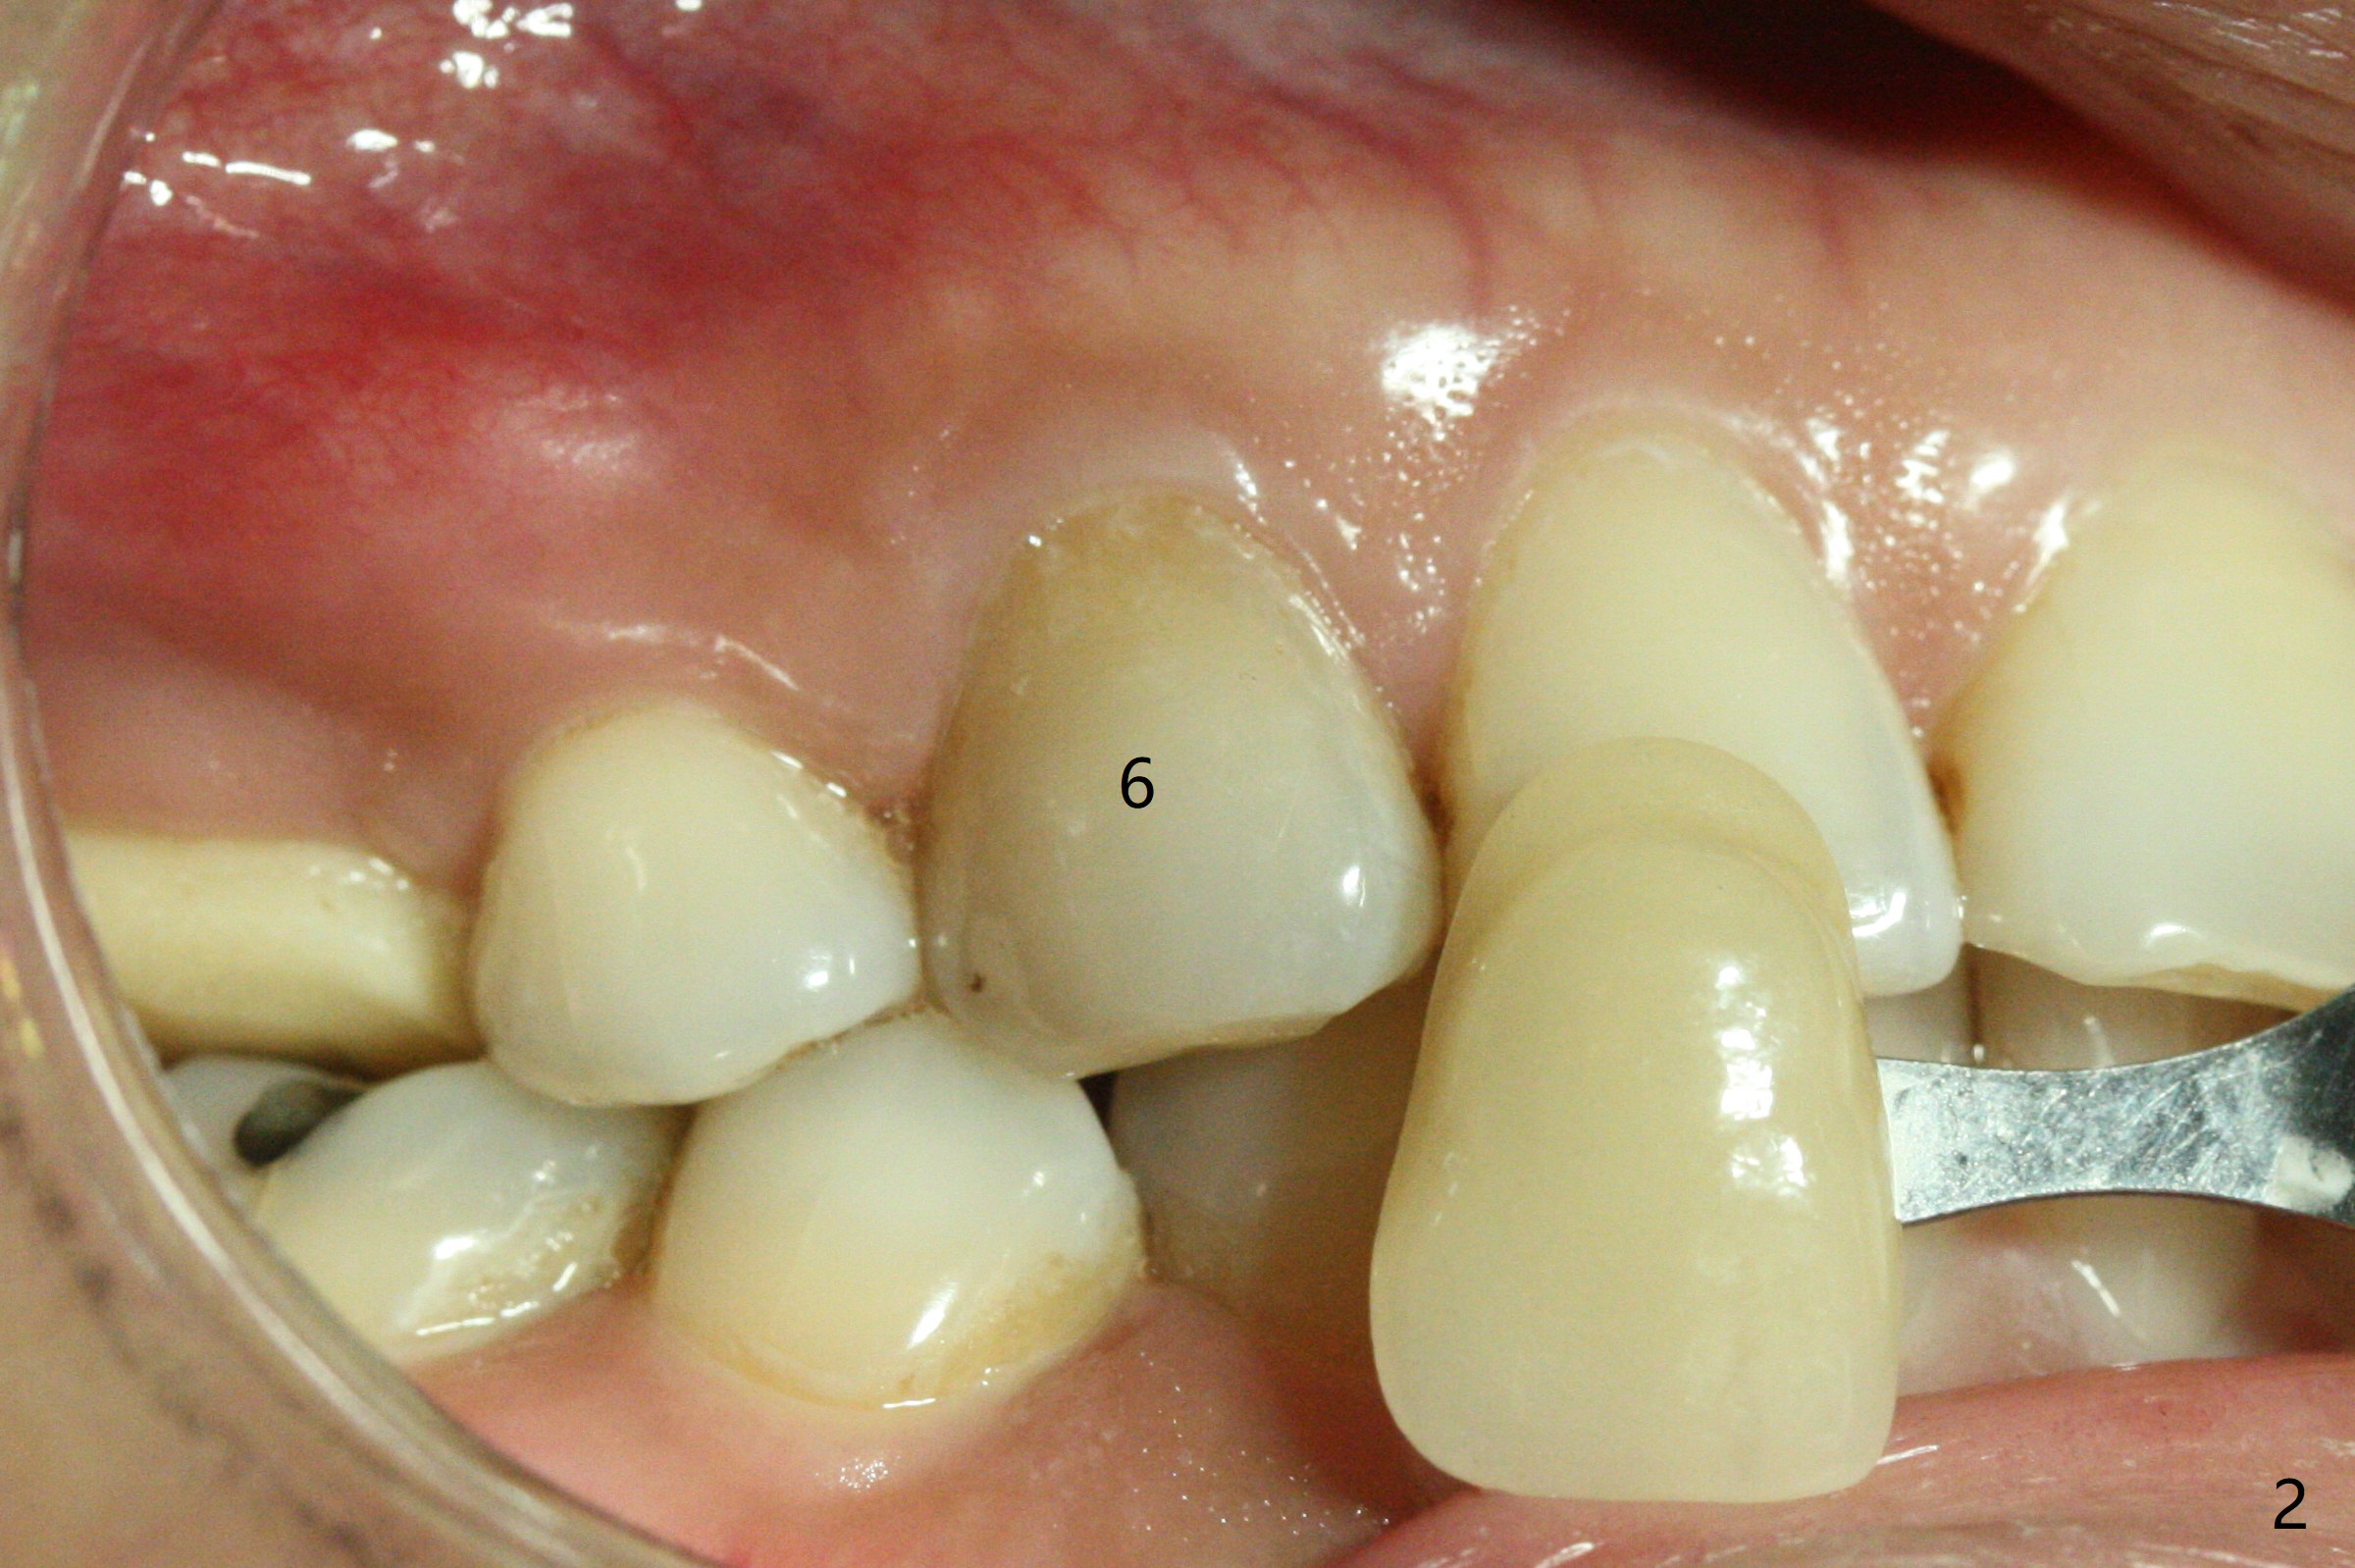

A 36-year-old woman (after #3 immediate implant and #31 socket preservation) wants to take care of the discolored canine 20 years post orthodontic treatment with extraction (Fig.1-3). RCT (Fig.4) appears to whiten the tooth (Fig.5 (A4)). The darkness appears to rebound 1 month post RCT, after removal of Gutta Percha for take home internal and external bleaching (Fig.6). The patient returns for composite after 3-week whitening (Fig.7,8). The shades of composite are bleach (flowable, C1) and B1 (packable, C2, Fig.9). The shade of the RCT tooth is compatible with that of the neighboring teeth 4 months post composite (Fig.10) when the implant at #3 has a new abutment.